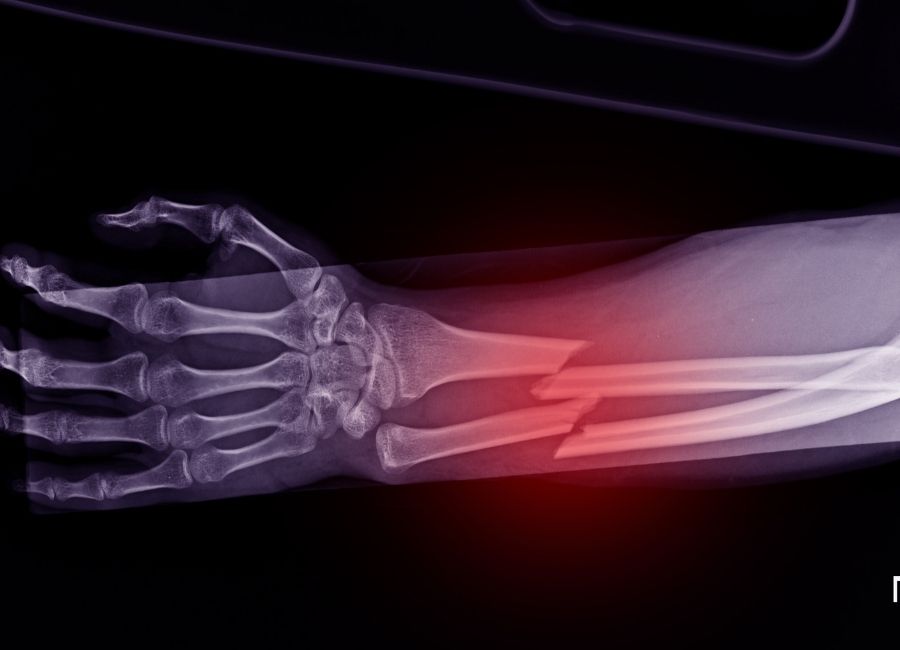

Bilek kırığı, günlük yaşamda sık rastlanan travmatik yaralanmalar arasında yer alır. Özellikle düşme, çarpma ya da spor esnasında bileğin üzerine alınan darbeler bu duruma yol açar. İnsan vücudunda en sık kırılan kemiklerden biri olan bilek, el fonksiyonlarının temelini oluşturur. Dolayısıyla bu bölgede oluşan hasar, kişinin günlük işlevlerini ciddi ölçüde etkiler. Ayrıntılı bilgi için bilek kırığı konusuna yönelik kaynaklar incelenebilir.

Bilek kırığı genellikle ani ve şiddetli ağrı ile ortaya çıkar. Kırık bölgesinde şişlik, şekil bozukluğu ve hareket kısıtlılığı görülür. Bazı durumlarda kırık açık hale gelebilir ve kemik dışarı çıkabilir. Bu tür vakalar acil cerrahi müdahale gerektirir. Tanıda röntgen çekimi en sık kullanılan yöntemdir. Ancak bazı karmaşık kırıklarda bilgisayarlı tomografi de tercih edilebilir.

Tedavi süreci kırığın tipine göre değişir. Basit kırıklar alçı veya atel ile sabitlenerek iyileşebilirken, parçalı veya ekleme uzanan kırıklarda cerrahi müdahale zorunludur. Cerrahi sırasında plak, vida veya tel gibi sabitleyici materyaller kullanılır. Bu yöntem, kemiğin doğru pozisyonda kaynamasını sağlar. Ameliyat sonrası süreçte ise fizik tedavi büyük önem taşır. Kasların zayıflamaması, eklem hareketliliğinin korunması ve bileğin eski gücünü kazanması için düzenli egzersiz yapılmalıdır.